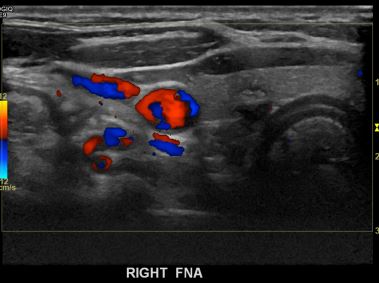

상기환자  외부 건진상 이상소견으로 내원하신 40대초반 여성분으로 의심스러운 갑상선 우엽 결절 세포검사진행후 갑상선암으로 진단되었습니다